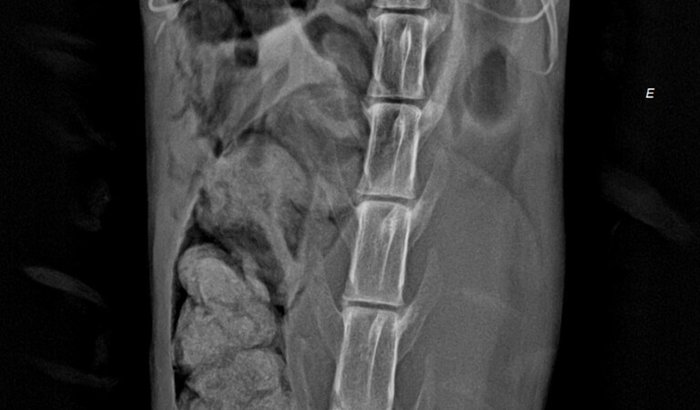

Esse é o Tito, um gatinho que resgatamos em uma situação extremamente delicada. Ele foi encontrado com prolapso retal e miíase intestinal — uma condição gravíssima onde larvas infestam o interior do corpo. Além disso, o Tito está com um fecaloma (acúmulo endurecido de fezes) que pode exigir cirurgia de emergência para ser retirado.